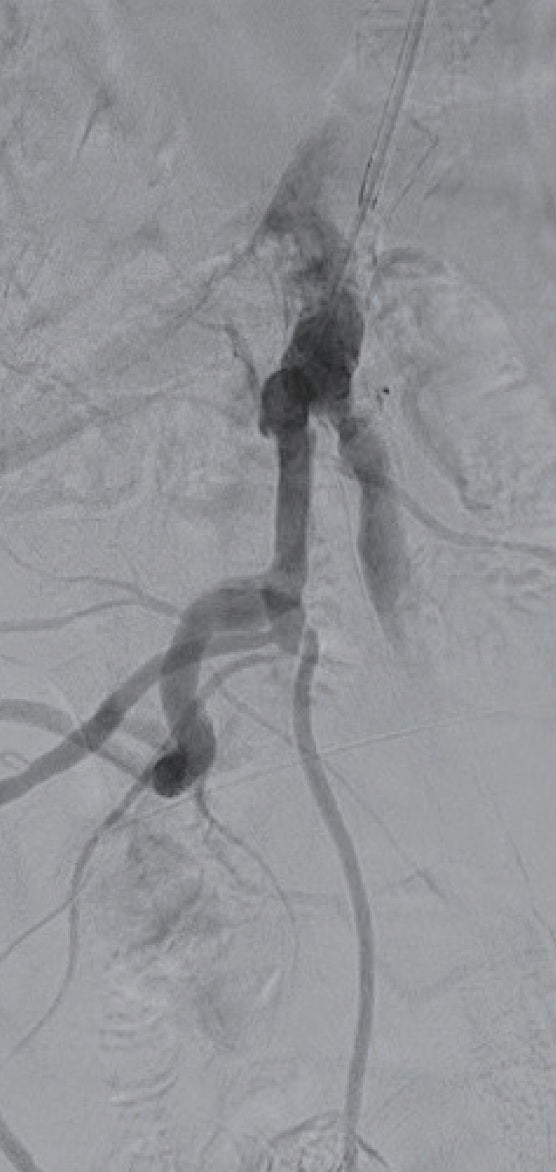

狭窄はないが高度石灰化があるため両側総大腿動脈からの穿刺を回避して左橈骨動脈アプローチを選択した。5 Frシースを留置後、型通りに腹部大動脈までシステムを下降させ造影を施行し、左外腸骨動脈起始部に高度石灰化病変を確認した(図1a)。

6 Frガイディングシースに変更しガイディングシースを左総腸骨動脈まで進めた。ガイドワイヤー通過は困難であったが、何とか0.014 inchガイドワイヤーを通過させて(図1b)、小径のバルーンで拡張後、IVUSで病変を評価した(図2)。全周性の表在型石灰化病変であり、通常のベアメタルステントでは拡張できないことが想定され、また内腸骨動脈との分岐部直下に置けるため、ステントグラフトの適応と判断した。6.0 × 40 mmのバルーンで拡張後、6 Frシステム対応のVBX ステントグラフト7.0 × 39 mmを留置、8.0 × 40 mmのバルーンで後拡張を実施(図3)した。IVUSで十分な血管内腔の確保を確認し(図4)、最終造影を行い、治療を終了した。穿刺からシース抜去までの手技時間は38分で、患者は車椅子で退室し、ベッド上の安静時間はゼロであった。足関節上腕血圧比(ABI)は術前の0.70から1.02まで上昇した。